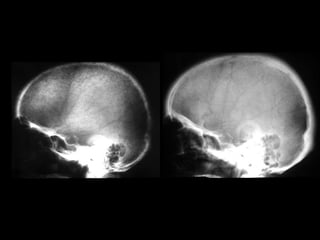

• The complication of rickets.

– Skeletal deformities.

– In neonates; posterior flattening and squaring of

the skull, or craniotabes, may be seen.

– In early childhood; bowing deformities of arms and

legs are common.

– Older children: scoliosis, vertebral end plate

deformities, basilar invagination of the skull may be

seen.